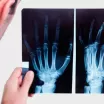

Periapikal kelimenin tam anlamıyla kök tepesinin etrafındaki alan anlamına gelir. Periapikal filmler, dişin kökünü detaylı görmek ve var olan sorunları tespit etmek için alınan radyografik görüntülerdir. Görünmeyen diş çürüklerinin, doku değerlendirmelerinin, gömülü dişlerin ve bunların pozisyonlarının, kistlerinin ve tümör oluşumlarının tespitinde erken teşhis için en avantajlı yöntemlerden biridir.

Periapikal röntgen; Dişlerin, çene kemiklerinin, dişeti seviyesinin X ışınları yardımı ile radyolojik görüntüsüdür. Röntgen çekilirken ağza yerleştirilen küçük film tutularak hasta tarafından dişe yaslanarak yapılır. Periapikal film, dişlerin tek tek görülmesini sağlar. Köklerin tek tek incelenmesini sağlayan periapikal röntgen filmi, tedavi öncesi tanıyı kolaylaştırırken tedavi sonrası kontrollerde tercih edilmektedir.

Hamilelik sırasında periapikal röntgen çekilmemelidir. Bebeğe zarar verme olasılığı çok düşük gibi görünse de kullanmamakta fayda vardır. Panoramik radyografilerde şüpheli durumlara göre daha detaylı görüntüler elde etmek için periapikal röntgenler kullanılır. Genelde şüphe duyulan birkaç dişin veya bu dişleri çevreleyen kemik ve dokuların detaylı incelenmesi için kullanılan periapikal film, detay avantajı ile hata payını azaltır.